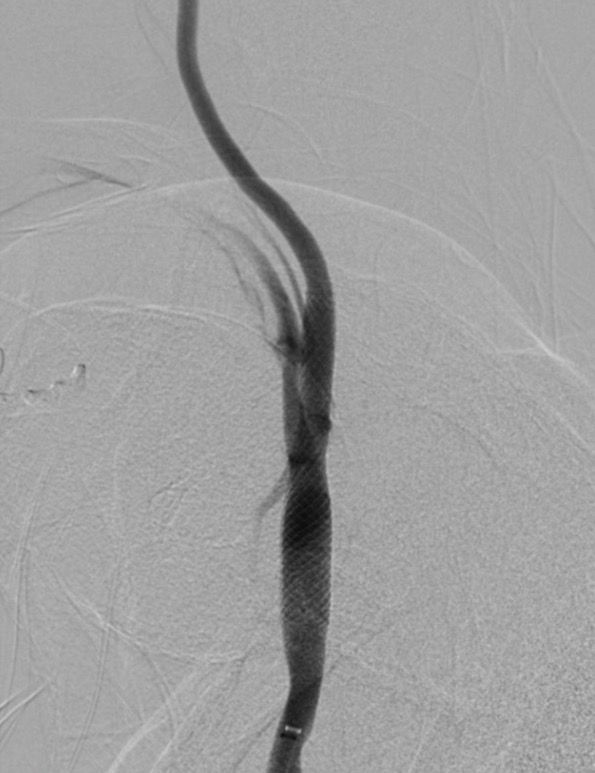

In >2,400 patients with ≥70% asymptomatic carotid stenosis on optimised modern medical therapy, adding carotid stenting almost halved the 4‑year risk of stroke/death vs. medical therapy alone (≈6.0% → 2.8%), with a number needed to treat of ~31 to prevent one primary outcome event over 4 years.

– The clearest incremental benefit in CREST‑2 was seen with stenting plus best medical therapy, while CEA showed only a modest, statistically non‑significant numerical advantage over medical therapy alone.

– All of this was achieved in expert, high‑volume centres with rigorously credentialed operators and very low peri‑procedural complication rates.